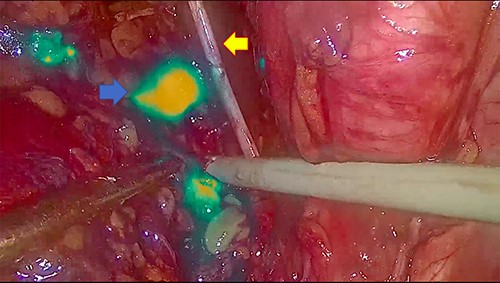

In November 2020, for a diagnosis of prostate cancer at prostatic biopsy, we intraoperatively performed ICG fluorescence-guided lymphography during a laparoscopic radical prostatectomy with pelvic lymphadenectomy. ICG was injected in the prostatic tissue of the patient transrectally through ultrasound identification of the gland. A fine needle was used connected to a 10 cc syringe, taking care to aspirate before injecting the tracer in order to avoid blood vessels. A dedicated laparoscopic high-definition camera system, provided by Karl Storz, was used in our case. This system allowed the surgeon to easily switch from White Light (WL) mode to ICG mode. For this reason, it was very simple to compare WL and ICG mode images. Furthermore, this technique is inexpensive, requiring only a small dose of ICG. Therefore, soon after ICG injection, the lymphatic vessels were identified in the pelvic cavity as fluorescent linear structures running side by side to the iliac vessels. Figure 1 shows the fluorescent lymph nodes in the obturator fossa. Then, using the ‘intensity map’ function (also called ‘overlay function’), lymph nodes can be seen as white structures as this function uses WL (instead of blue light) and eliminates the colors, as shown in Fig. 2. Surgical dissection was therefore performed, avoiding iatrogenic damage to major lymphatic structures. On histological examination, the prostate gland was found to be affected by an acinar adenocarcinoma (with Gleason Score 8, 4 + 4) involving ~20% of the right lobe and 35% of the left lobe. Twenty-four lymph nodes sent as obturators (15 on the right and 9 on the left side) and 10 lymph nodes sent as external iliacs (6 on the right and 4 on the left side) were free from metastases. The patient was discharged 5 days after surgery, and 6 months after surgery, he did not show any complications related to lymph node dissection.

Panel (A) shows the lymph nodes in green color when the blue light is used. Panel (B) shows the lymph nodes in white when the ‘overlay’ function is used.